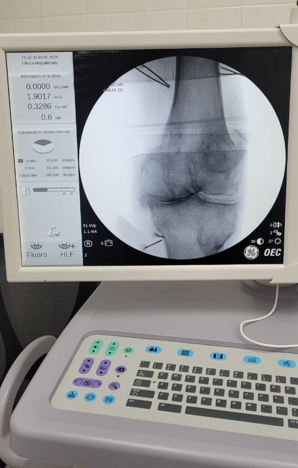

Paciente con dolor intenso por artrosis severa de rodilla

Candidato a un reemplazo total de rodilla, el paciente sentía un dolor tan intenso que le impedía la marcha.

Por la morbimortalidad de la cirugía, se procede a realizar en Tidol un tratamiento con radiofrecuencia, debido al dolor intenso que le impedía la marcha.